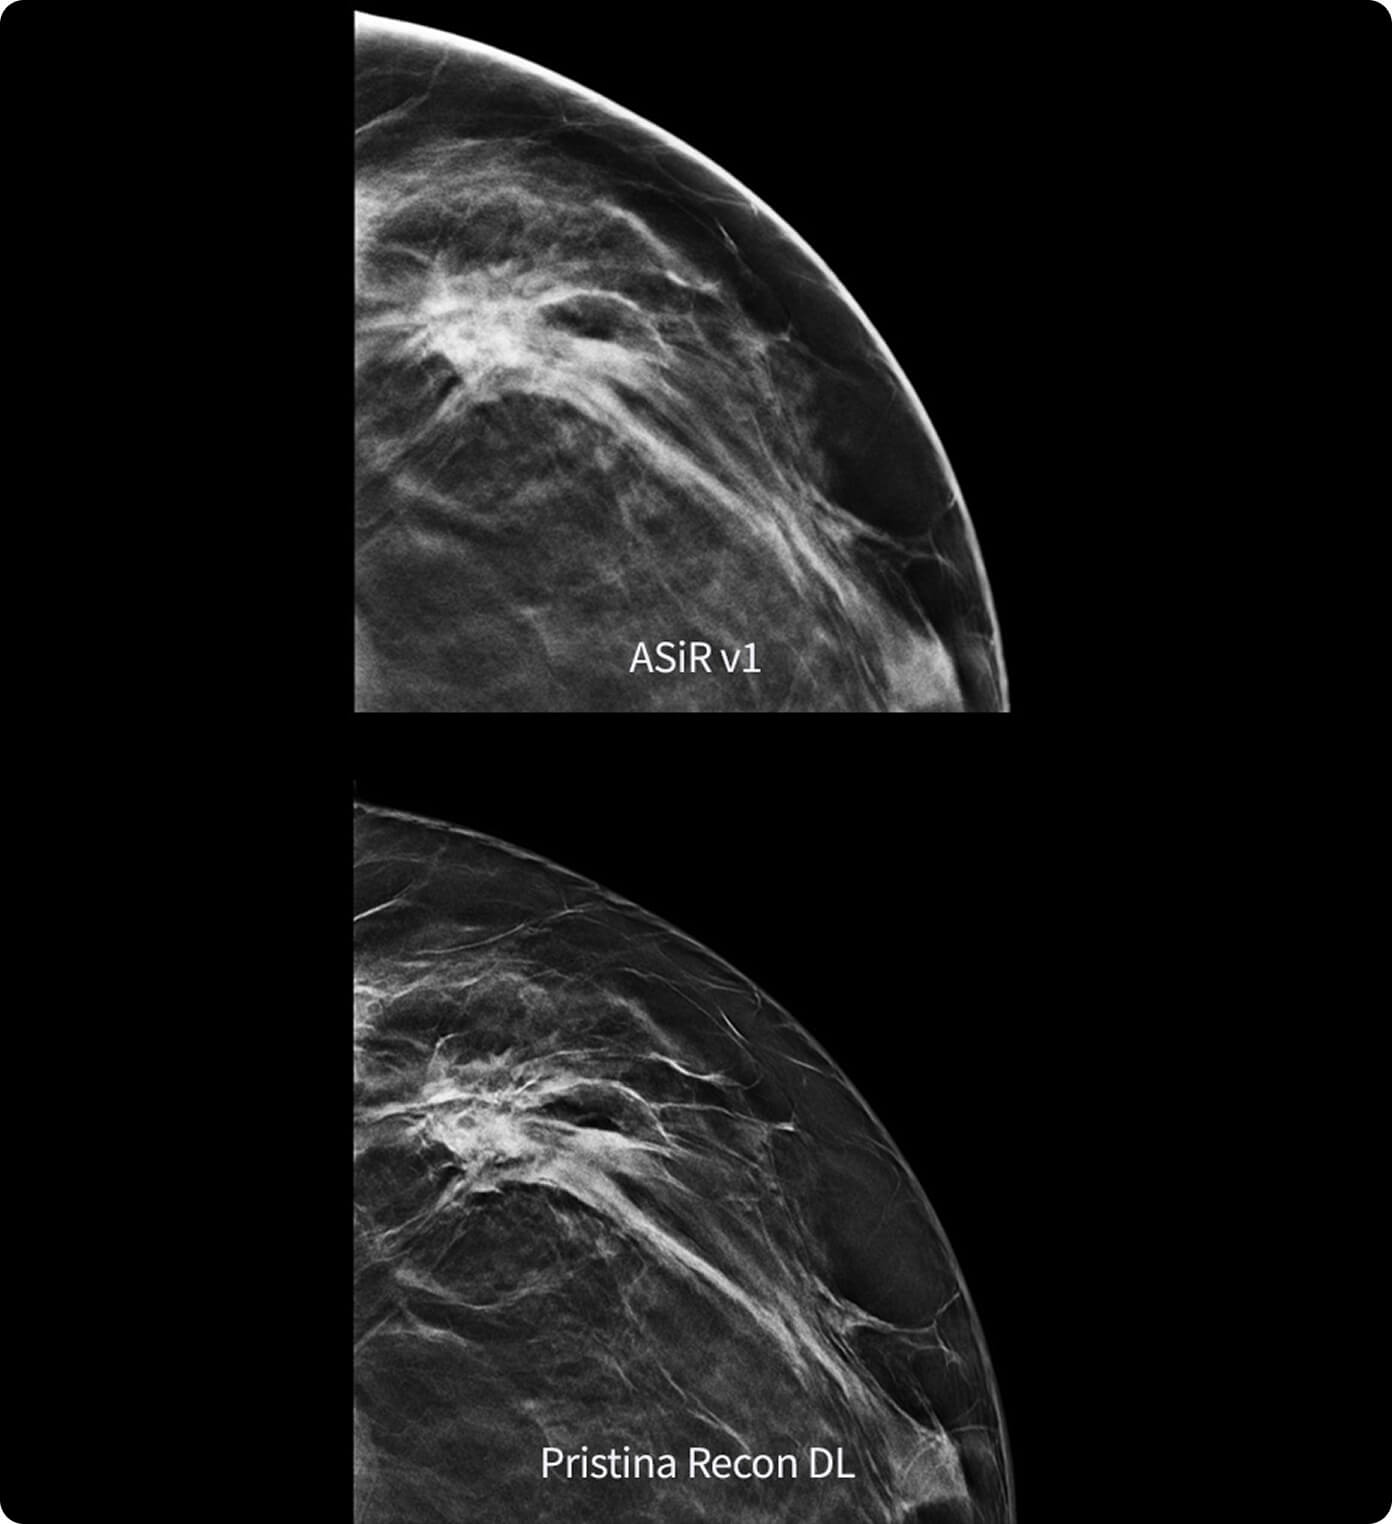

Reveals fine details minimizing artifacts and perceived noise1

Sharpness and overall IQ preferred in more than 99% of the image reviews1

Its dual deep learning technology reveals fine details minimizing artifacts and perceived noise1,2, without increasing dose.

Pristina Recon DL reconstructs with scientific precision, transforming breast images into pristine, clear volumes. It uses two deep learning models to improve image quality without changing the acquisition.

The improvement is easy to see, with radiologists surveyed consistently preferring its sharpness1,2 and lesion conspicuity1,2.

1. Preference study performed on 140 study cases with 8 MQSA-approved radiologists, trained on clinical image quality by ACR, comparing Pristina Recon DL to ASiR v1.

2. Reader performance evaluation on 19 680 reads with 8 readers using modeled clinical data comparing Pristina Recon DL and ASiR v1.